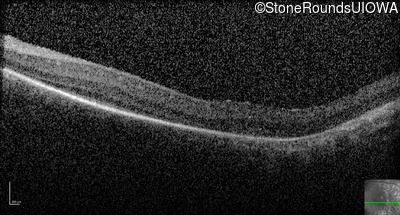

Optical Coherence Tomography - Right -

No Light Perception

Exemplar

Expanded OCT Stack

×